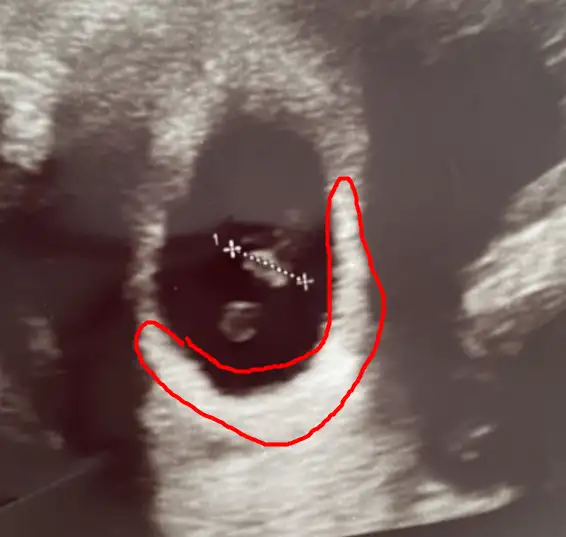

Karından ultrason bu arada

plesantası sağda bu yüzden kız aşkım :D

Bu bebişler neden hep ortada durur anlamadım azıcım plesentaya yakın dursalar olmuyor sanki 😂😂😂 kız gibi kuzum saglıkla gelsin inşallah başka var mı foto

Birde şöyle var tek olan diğer foto bide ikisini attım